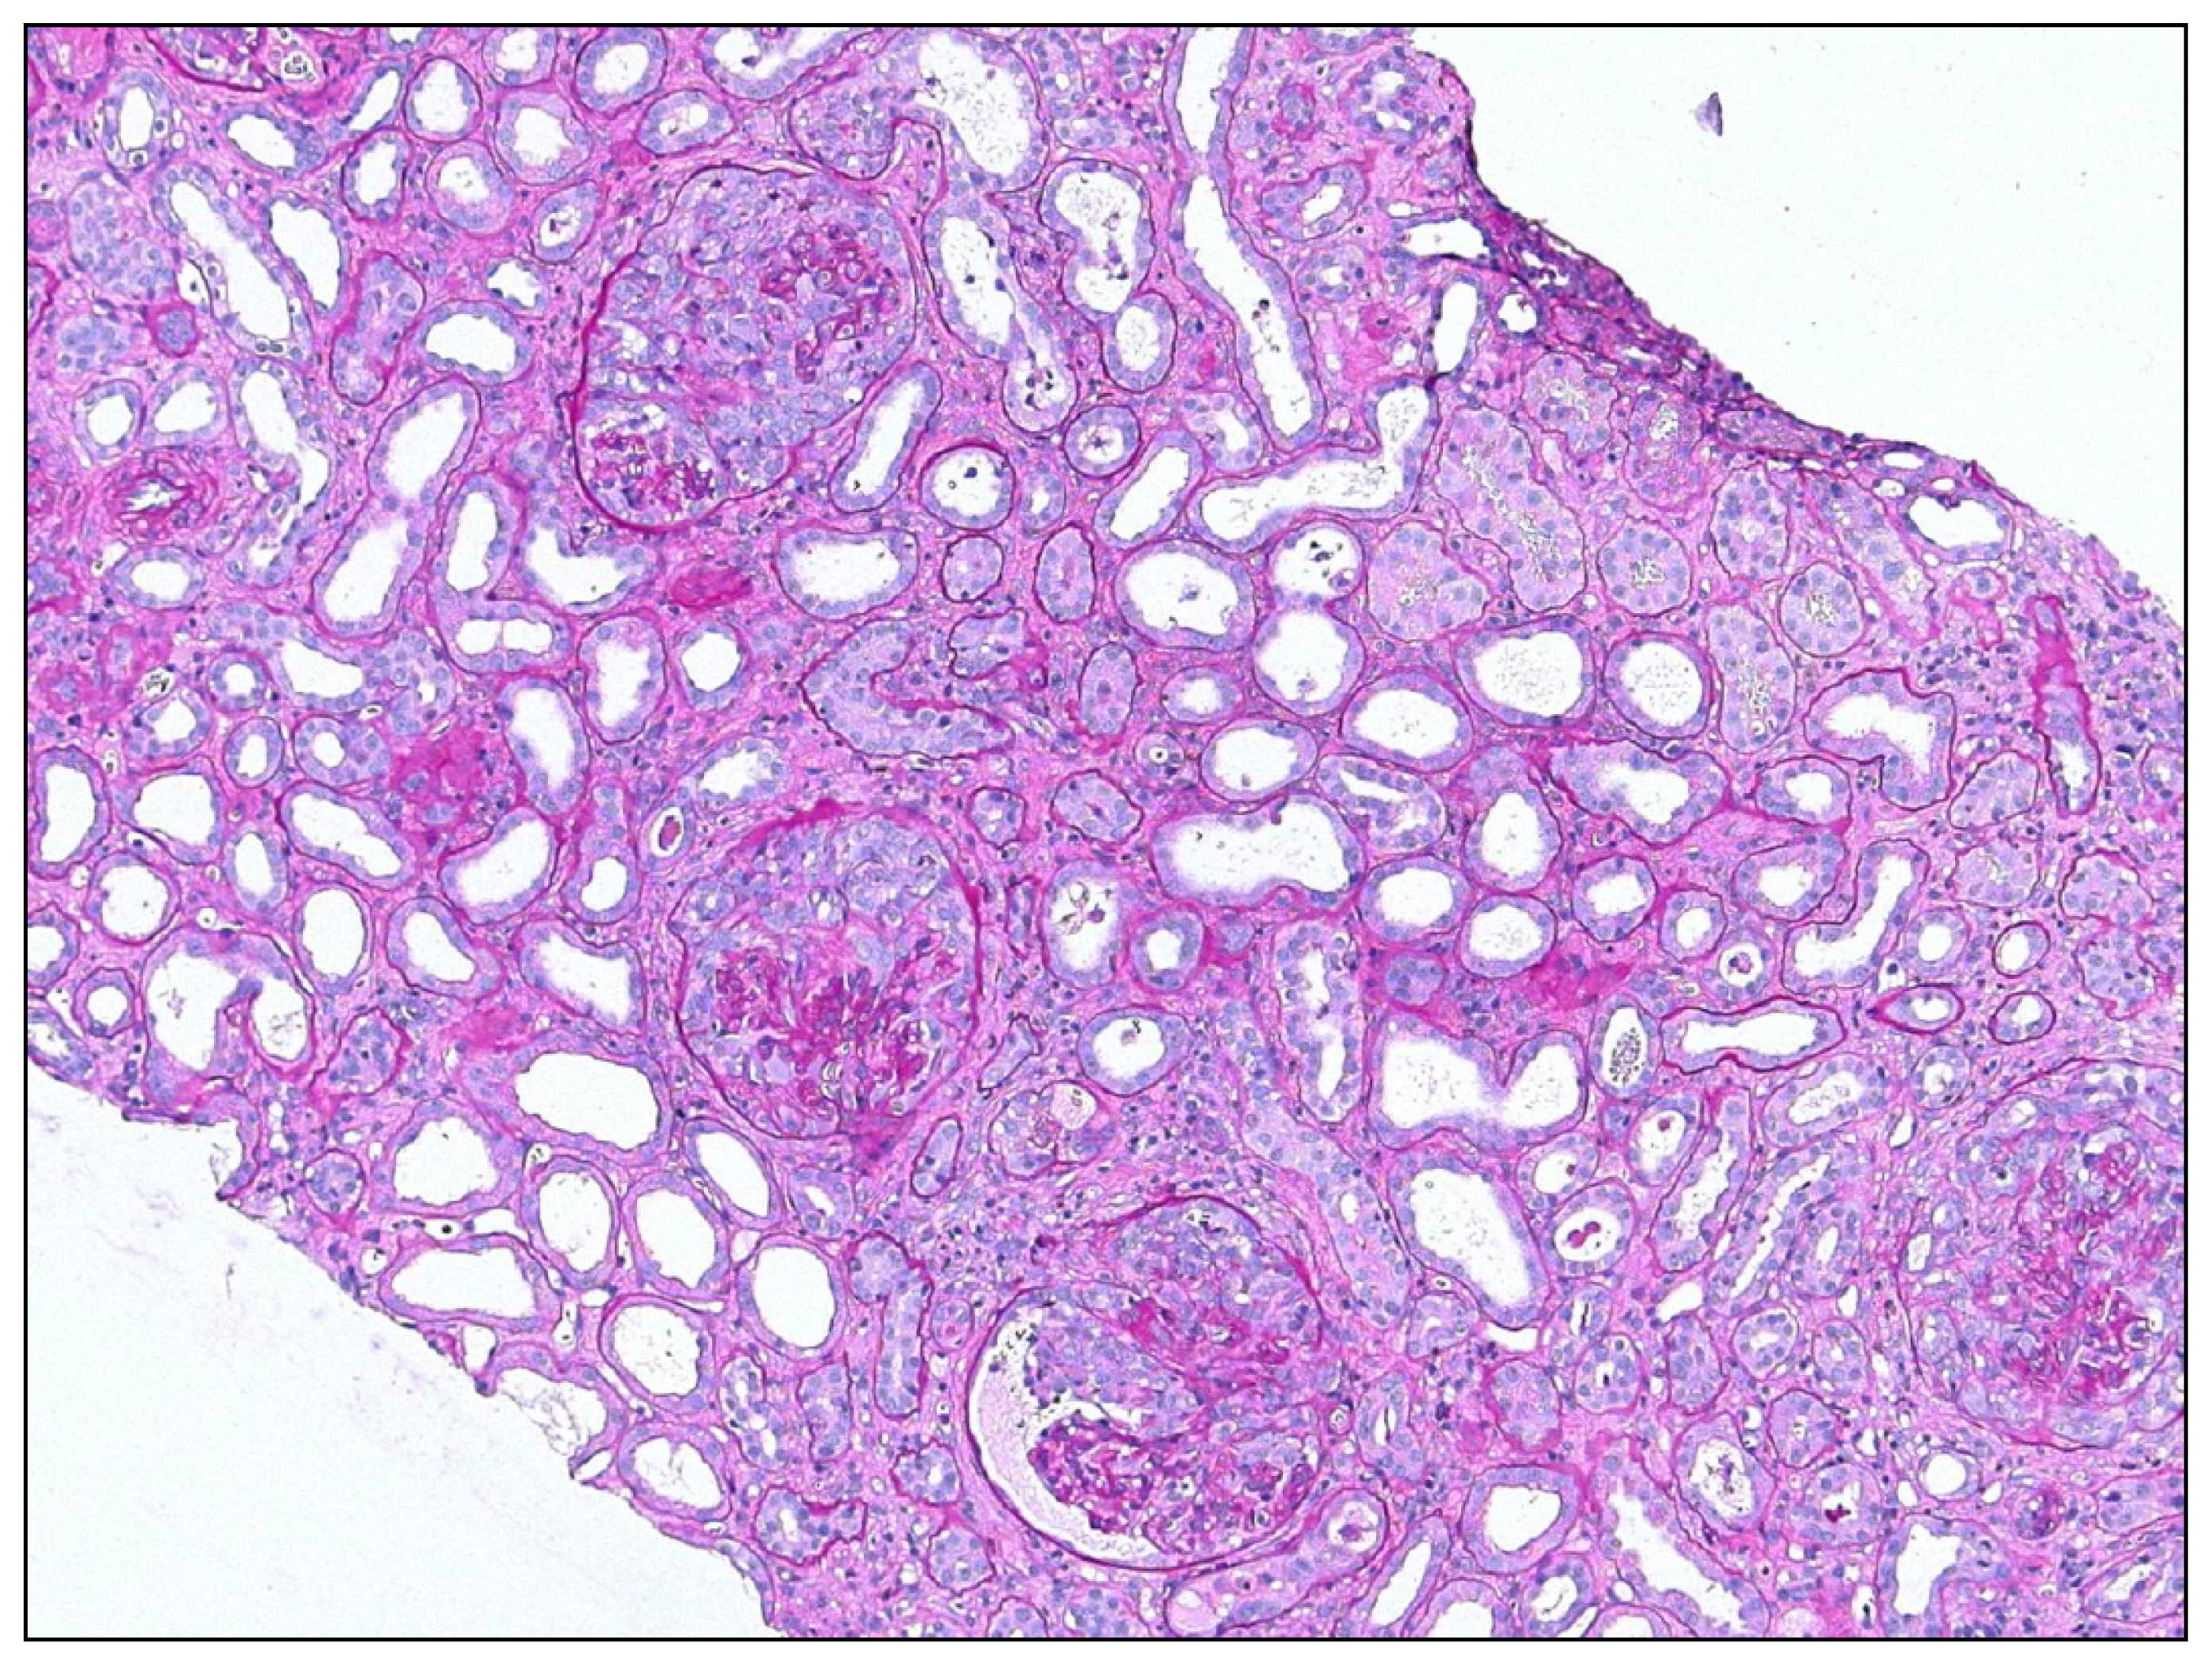

5.1. Overshooting Epithelial Regeneration in the Kidney

5.2. Insufficient Epithelial Regeneration in the Kidney